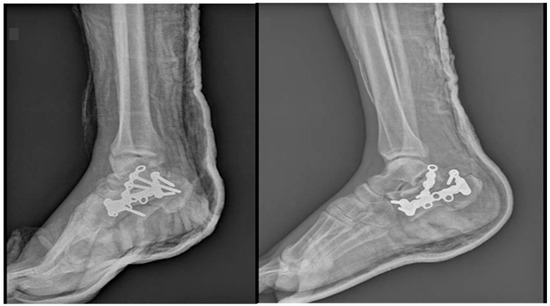

Background: Covering the defects around the calcaneus is still a largely debatable subject. In the classical view, the defects at the level of the foot can be treated only by a free flap. In a modern approach, it has been observed that for small or m...